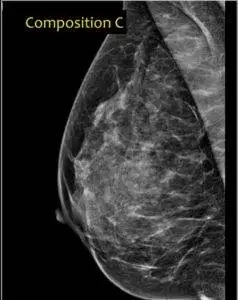

Cat. C: Heterogeneously dense Breasts.

This represents another 40% of women’s breasts. A mammogram reveals an even spread of fibroglandular density throughout the breast. This is the point from which we regard a breast as being dense. Small tumors can be missed in a mammogram as a result.

There was no way I could discuss dense breasts specifically, without showing you images. Therefore I obtained all these images from “Radiology Assistant”, of the Netherlands and I am grateful.

They were very thorough on this subject and included an exciting approach I liked, in distinguishing the categories mentioned above.

Category. C: 50 -75% Fibroglandular.

However, the bottom line is that even if your mammogram chiefly falls under category B but there are areas in your mammogram that are bright enough to obscure small masses, it is regarded as category C. This means you have dense breasts.